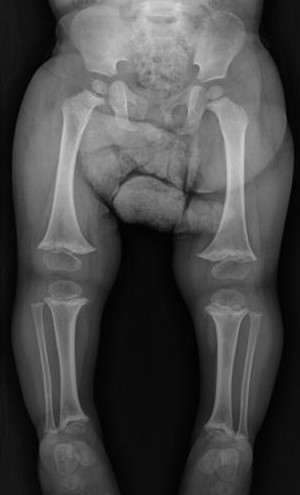

Displasia metafisaria múltiple. Reporte de caso

Jennifer Richardson Maturana, Martha E. Oyuela-Mancera, José A. Ovalle-Barranco

28-32